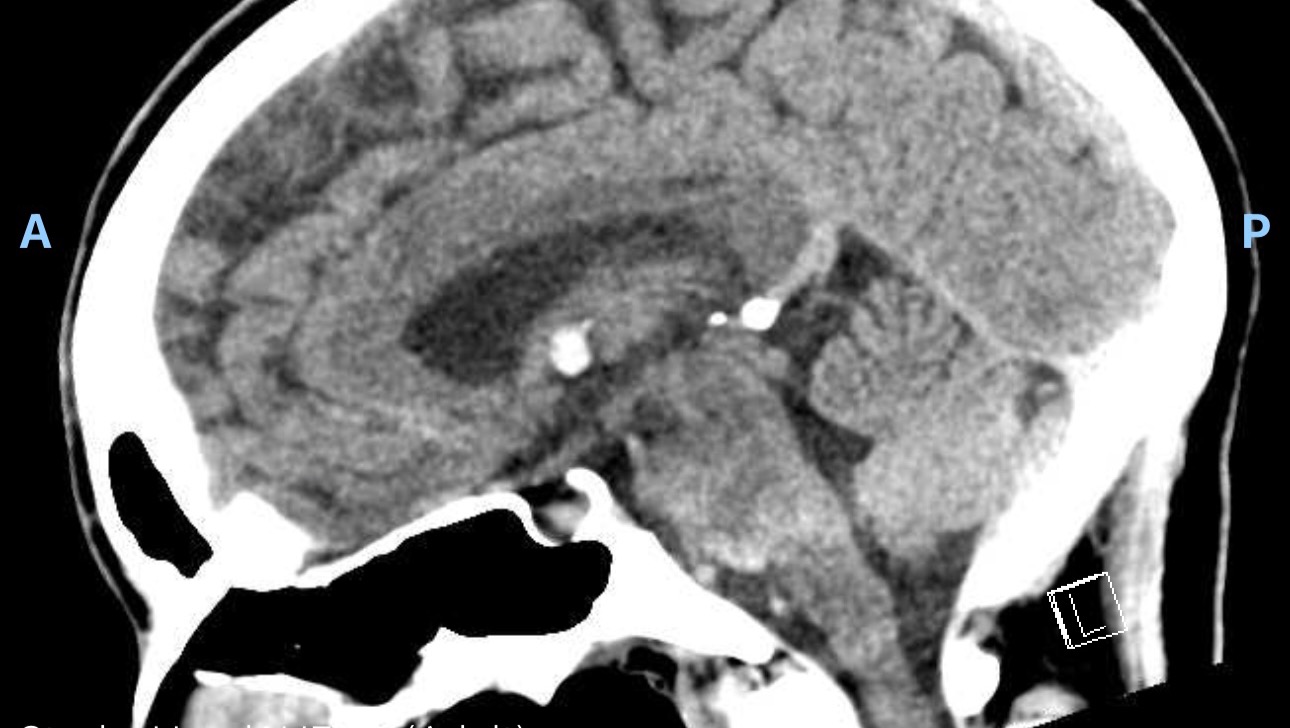

The ED doctor came into my room and squatted down beside me; instantly, I knew something was wrong. "Has anyone told you yet the results?" he asked. I said no... and he continued to tell me that they found an 8.1 mm tumor in the 3rd ventricle of my brain, called a colloid cyst.

A colloid cyst is a benign, slow-growing brain tumor that's filled with a gelatinous material called colloid. It's not cancer. It's thought to form when you are growing in the womb and usually doesn't present issues until your 30s/40s. It's the most rare type of brain tumor and makes up 1% of all brain tumors; 3 in a million people are affected by this type of tumor. It usually doesn't cause people issues until it grows to the point of blocking CSF (cerebral spinal fluid) drainage or starts pressing against structures in your brain.

This is why I have had this headache. Neurosurgery was consulted and after an MRI for better pictures, it was diagnosed as a colloid cyst. The only solution is to have it removed via endoscopic brain surgery.

The team at DHMC didn't seem very concerned because my neuro exams were normal and the only symptom I have is a headache; however, in the same sentence, they told me the worst thing that could happen is sudden death from acute hydrocephalus (build-up of CSF causing brain swelling, loss of consciousness, and subsequently death). I was already so overwhelmed by everything I didn't ask too many questions, but after sitting with this diagnosis for a couple of days and doing a lot of research, the fact that I have a constant headache and the increased headache when I do anything that raises my blood pressure means that the cyst is temporarily blocking the drainage of CSF, building up that pressure, causing the headache to be worse.